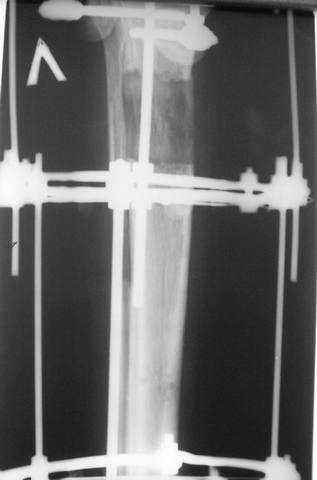

3,4 - через 4 недели наложен спице-стержневой аппарат, произведена остеотомия большеберцовой кости в верхней трети, раны зажили, проводилась дистракция в аппарате.

5, 6 - через 2,5 мес после травмы выполнен закрытый остеосинтез блокируемым штифтом.